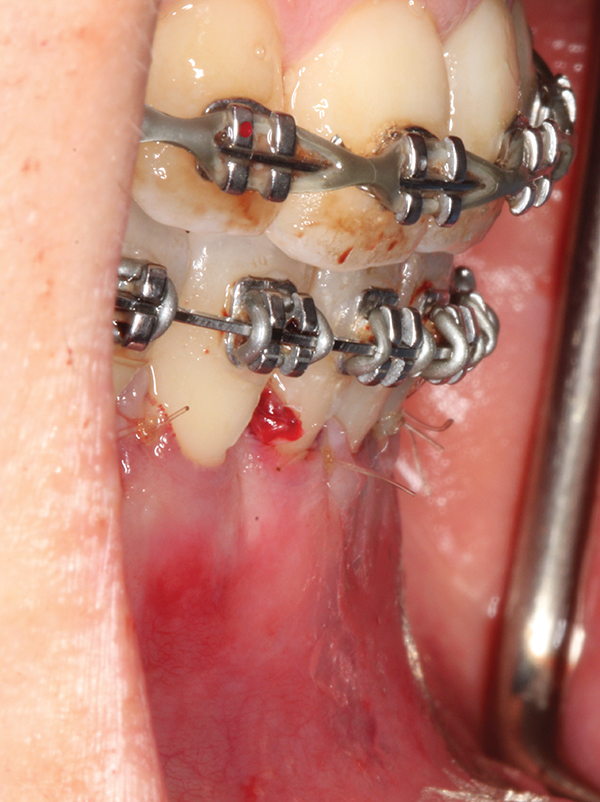

Fig 4. Particulate corticocancellous mineralized freeze-dried bone allograft in place on the left half of the mandible for periodontal regeneration and alveolar augmentation.

Figure 4

Fig 5. Bone grafting complete. Collagen wound dressing in place for graft stabilization and autogenous connective tissue grafts in

place, teeth Nos. 21 and 22 and Nos. 27 and 28, for simultaneous soft-tissue augmentation.

Figure 5

Fig 6. Tension-free wound closure.

Figure 6